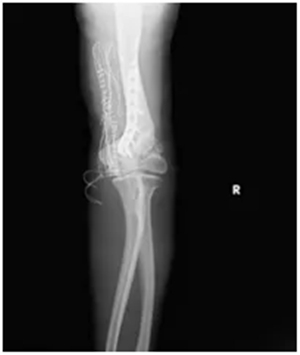

第二步“肱骨截骨矫形+钢板固定”:通过精准截骨,纠正肘关节的外翻畸形,再用钢板牢牢固定,让关节恢复正常的力学结构。

肘关节外翻角度从术前的30°左右,成功矫正到10°左右;

X线复查显示:钢板固定位置十分合适,骨头对位良好;